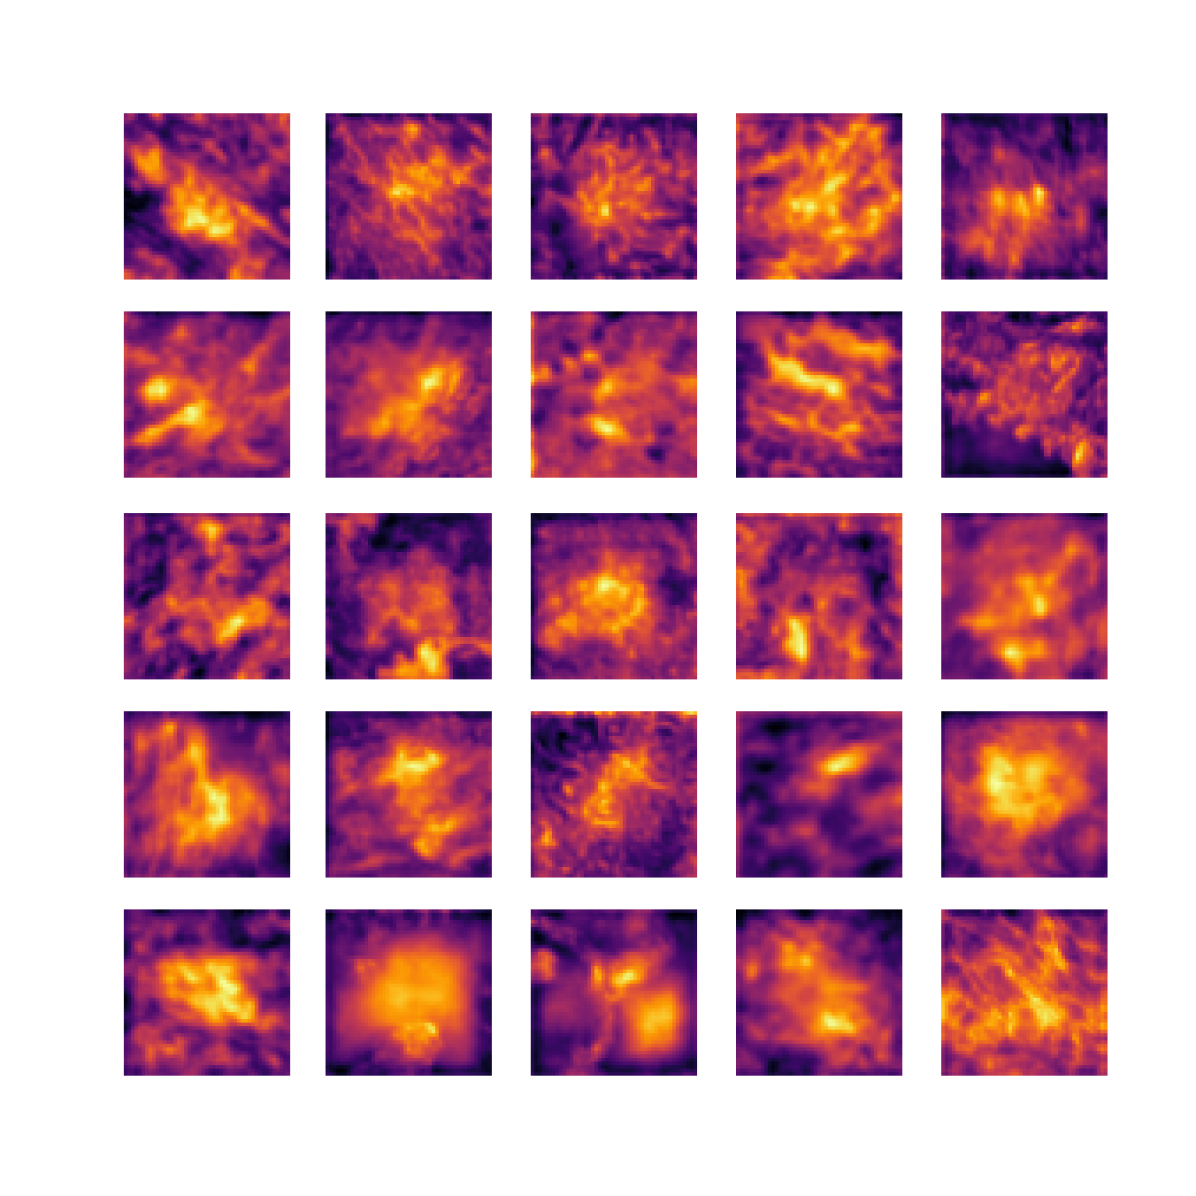

We also analyse the activation maps for each model using GradCAM as described in section S3. This offers more insight into the areas of the image which are contributing most heavily to the models’ representations. In Figure 4(b) we present some representative examples, however, a larger selection which was chosen at random is presented in Figures S10 to S25. The larger selection makes it easier to see the emergent patterns, including that privileged Siamese models tend to mainly identify features which are strongly present in both inputs, while unprivileged Siamese models tend to learn more diffuse features that are not specific to one cell phenotype or image region. TriDeNT ♆ incorporates both sets of features, learning both features specific to the privileged data and more the general features associated with unprivileged Siamese networks.

We can see in Figure 4(b) panel A that for ERG, the privileged Siamese model focuses almost exclusively on any nuclei which could be endothelial cells. As there are very few endothelial cells in the dataset, it could be an effective strategy to identify anything that could potentially be an endothelial cell to minimise the difference between the representations of the H&E model and the IF mask model. In the corresponding unprivileged Siamese image, we see that the model identifies some of these nuclei, albeit less strongly, but also focuses heavily on the other tissue and even the background, while strongly fixating on two spots of debris in the center of the image. This model has less ‘incentive’ to learn the weak features related to endothelial cells as these occur rarely and are not easy to detect, while more generic strong features such as the presence of connective tissue and the prevalence of background are more common and predictable from augmented images. We see that TriDeNT ♆ combines these two feature sets, strongly identifying nuclei while also identifying the connective tissue.

In panel C we see a similar pattern, with the privileged Siamese model fixating solely on the nuclei, while the TriDeNT ♆ model takes a more balanced approach. The unprivileged Siamese model appears to focus on a single cluster of nuclei while neglecting others, and similarly identifies an area of fibroblasts with its distinctive pattern but does not others.

In contrast to panels A and C which represent models with poor privileged Siamese results, panels B and D represent models whose privileged Siamese results were comparable to both TriDeNT ♆ and even the supervised baseline. It is therefore interesting to note that there are far more similarities between the privileged Siamese and TriDeNT ♆ models in both cases. Particularly in panel B, TriDeNT ♆ and the privileged Siamese model return virtually identical heatmaps, with both strongly identifying epithelial nuclei and neglecting the same areas of connective tissue. The unprivileged model in this case appears to focus solely on the centre of the image, giving a significantly different heatmap to the other panels.

Panel D again shows the previous pattern, with the privileged Siamese model identifying the features strongly present in the privileged data – fibroblasts – while neglecting the nuclei present. TriDeNT ♆ also strongly identifies the connective tissue, but, unlike the privileged Siamese model, does not completely neglect the nuclei. The unprivileged Siamese model primarily identifies background, and does not appear to identify the nuclei in this example.